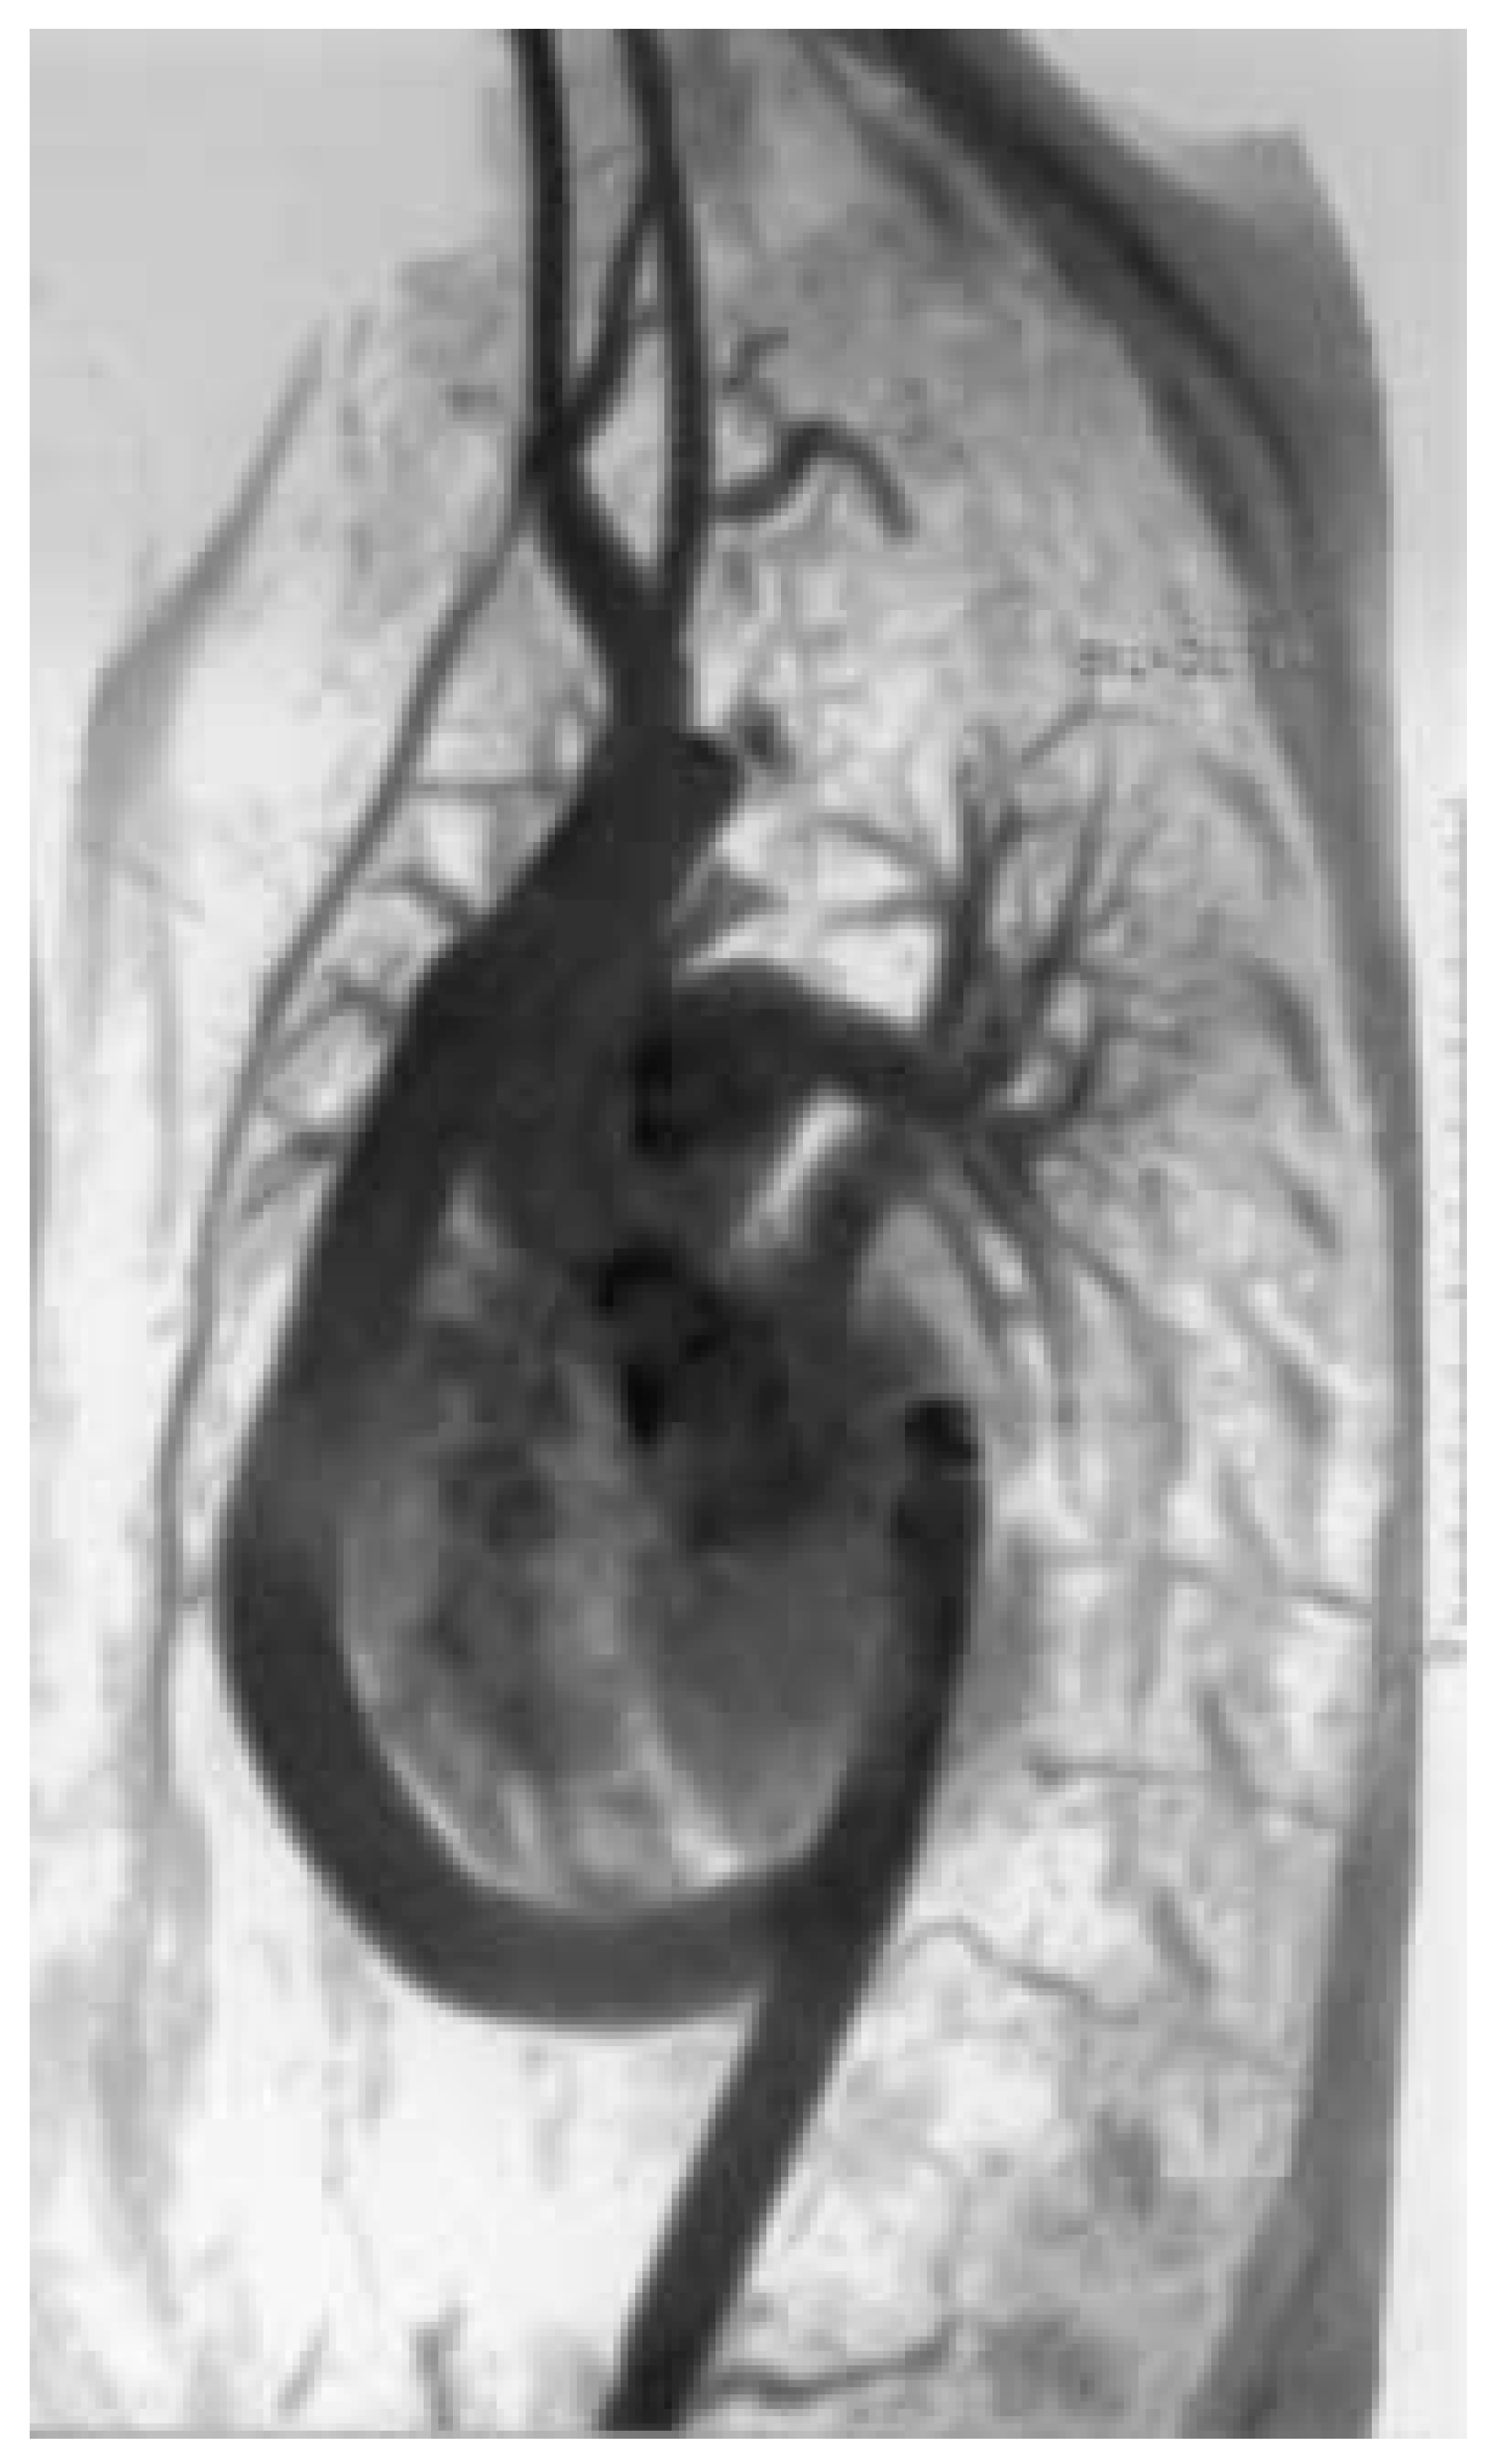

The young patient with coarctation recovered extremely well without any cardiac, neurologic or bleeding complication and was discharged after one week of hospitalisation. At 6 months follow-up she did well and had a normal blood pressure (systolic pressure 110) both at rest and at exercise under a mild dosage of beta-blocker. Postoperative magnetic resonance imaging demonstrated a patent aortic bypass and the complete exclusion of the pseudoaneurysm (Figure 7).

Figure 7.

Postoperative MR-angiography shows the patent ascending-to-descending aortic bypass, an ascending aorta-to-left carotid bypass and the transposition of the left subclavian artery to the left carotid artery.